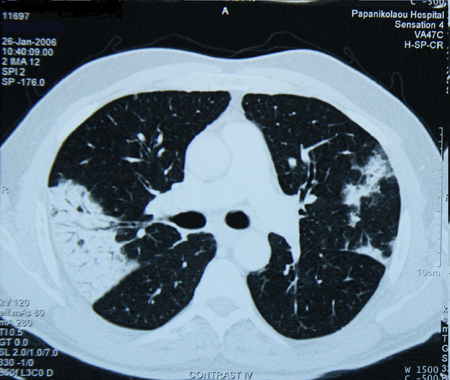

Chest CT of a patient with amiodarone pulmonary toxicity, showing asymmetric opacities with a peripheral distribution

From the personal collection of Dr A. Pataka and Professor P. Argyropoulou, Aristotle University, Thessaloniki, Greece